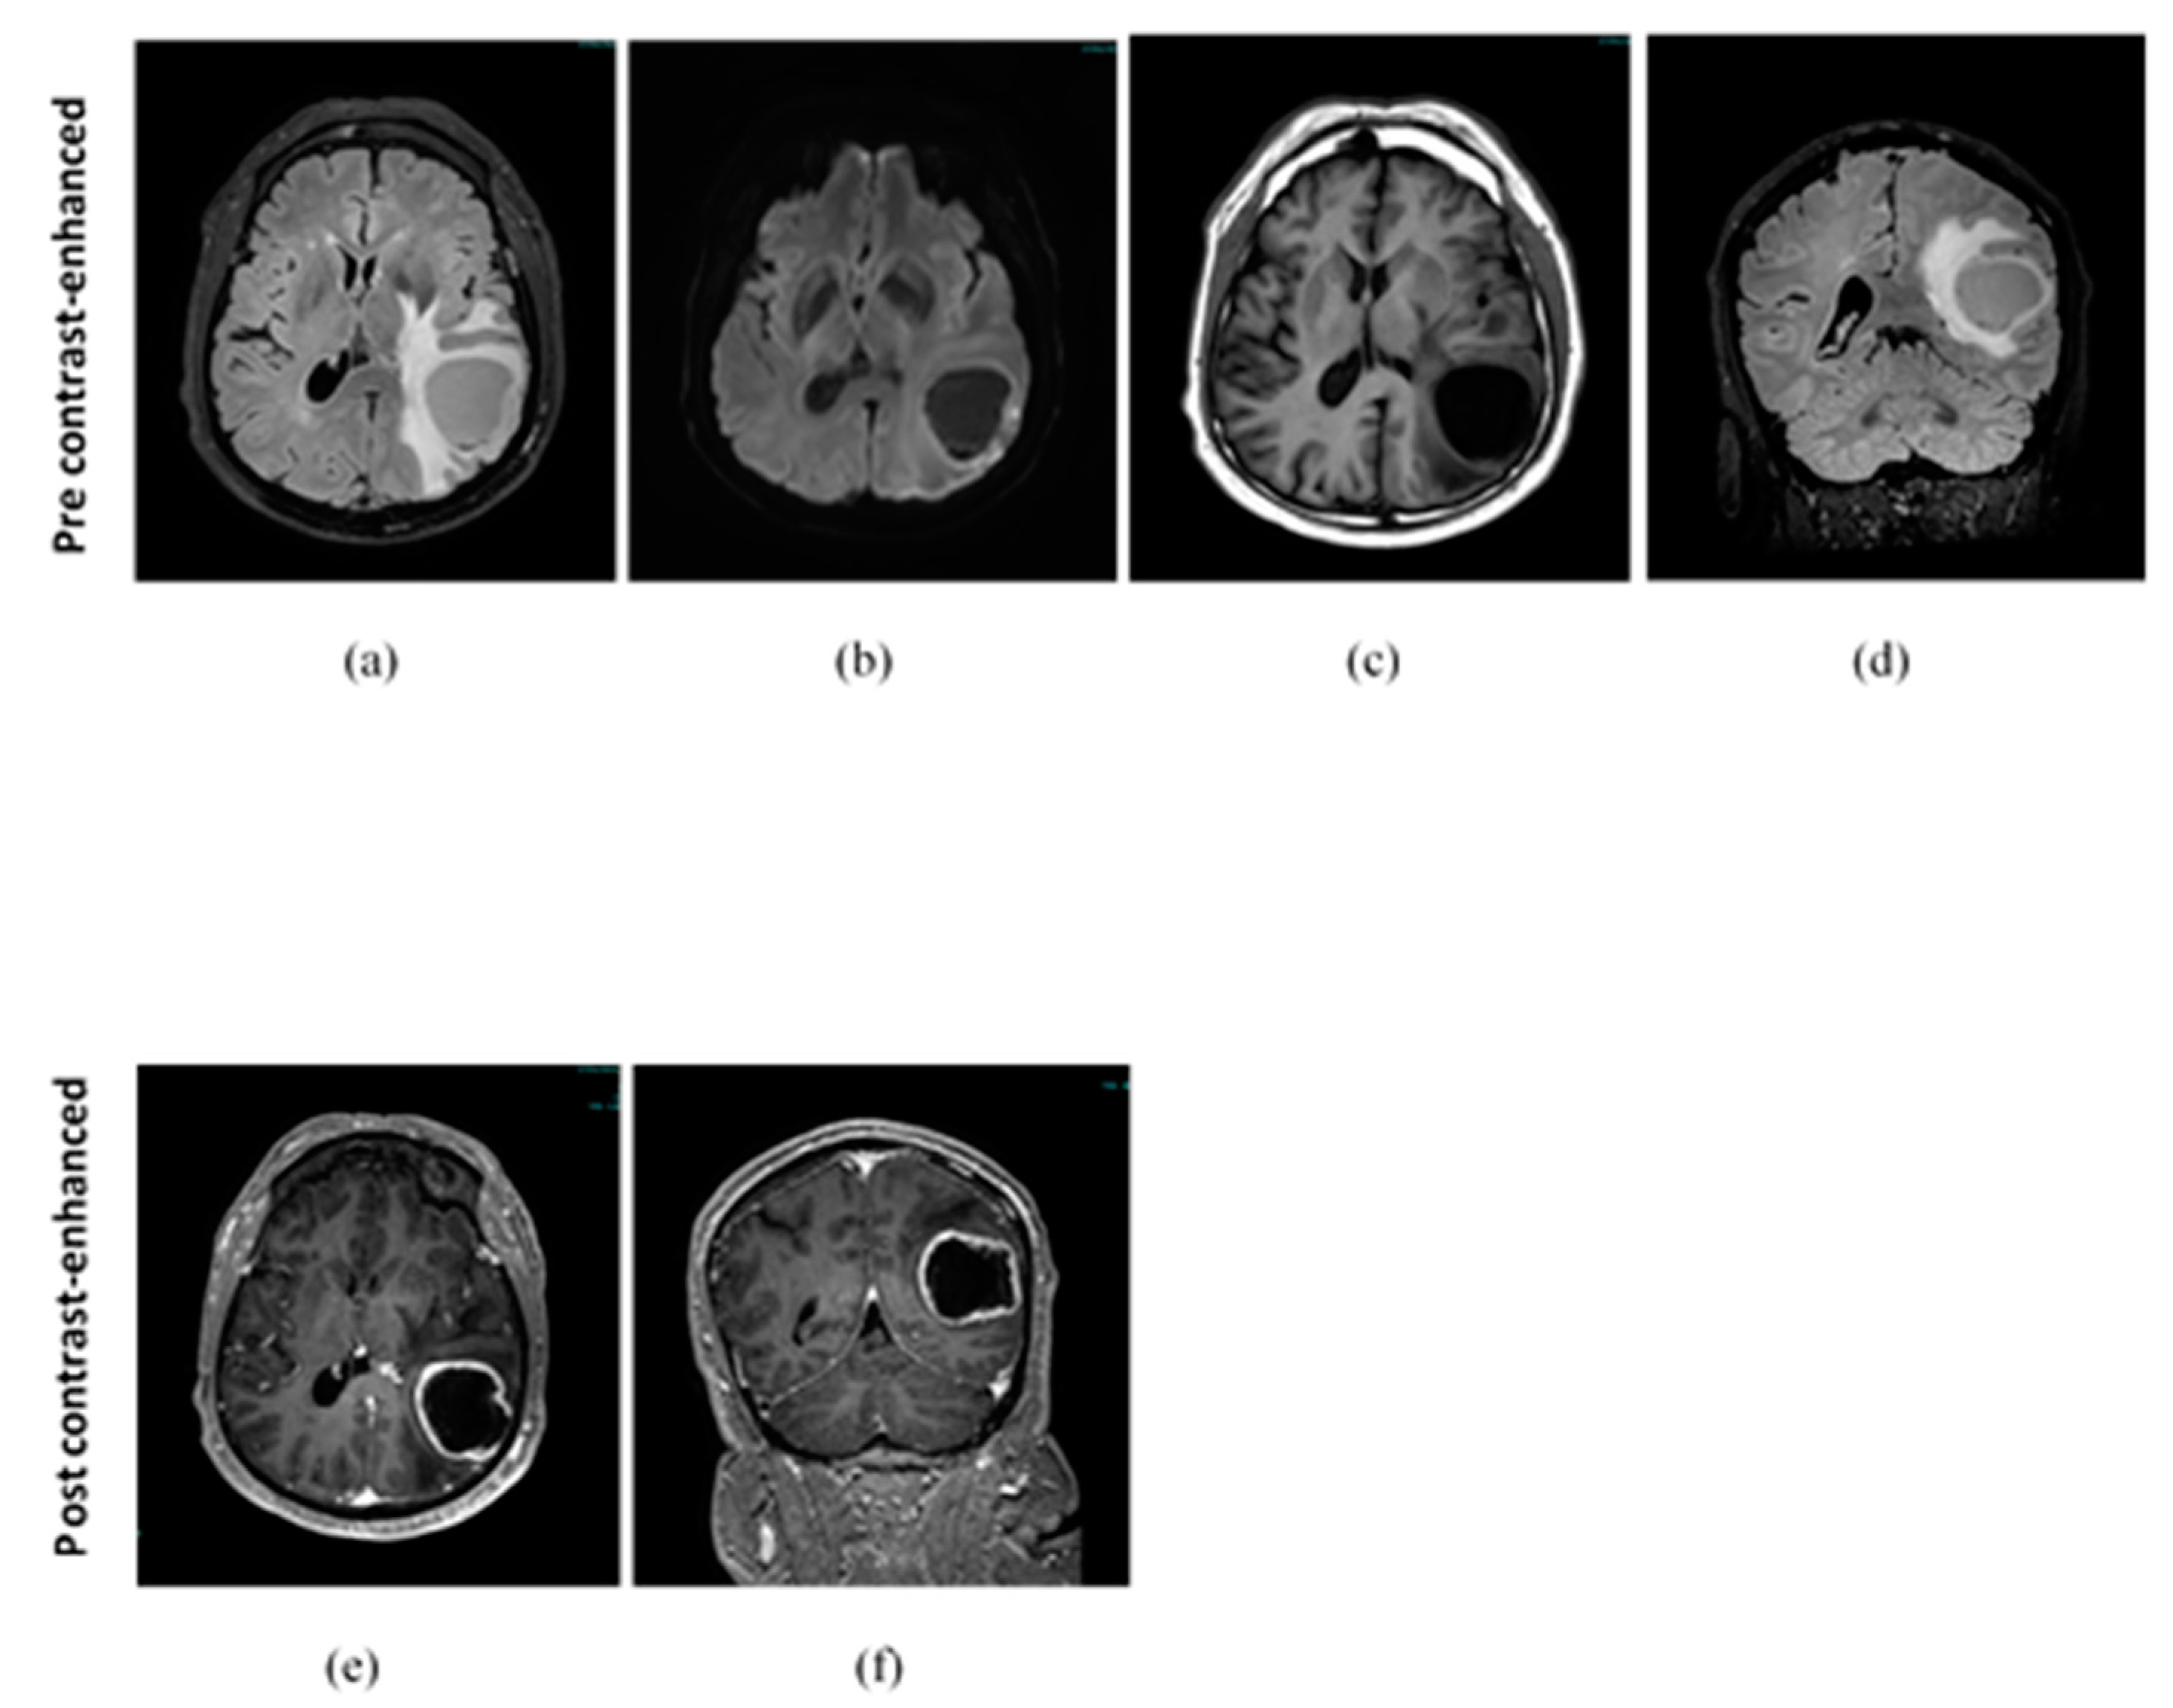

3.2. Clinical Findings